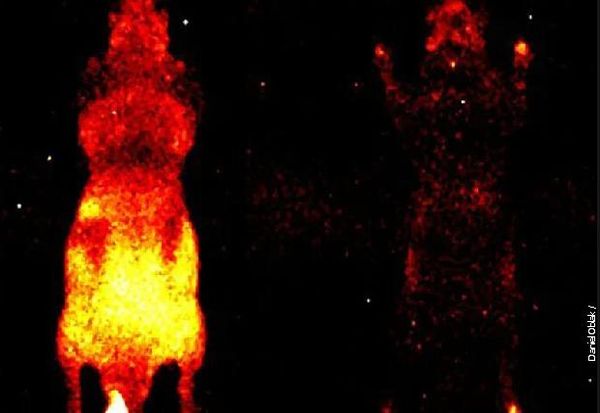

Истражувачкиот тим предводен од проф. Даниел Облак од Универзитетот во Калгари користел високочувствителен дигитален систем за снимање. Тие сместиле глувци во затемнети, контролирани комори и ги снимале два часа. Кај живите глувци регистрирале сјај по целото тело, особено над органите, главата и шепите. Кај мртвите глувци светлосната емисија целосно исчезнала.

- Живите глувци емитуваат јасно изразена ултраслаба емисија на фотони, што укажува на активни биолошки процеси, додека кај мртвите глувци емисијата е речиси недeтeктирана - пишува во трудот.